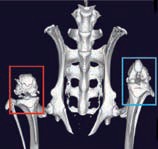

GX IIIは、マウスから小型ウサギまでのさまざまな種のin vivoイメージングだけでなく、より高解像度なex vivo イメージングも可能となり、さまざまなサンプルをより最適な測定方法で撮影できる幅広い柔軟性を提供します。

- 5種のFOV:8mm, 18mm, 36mm, 72mm, 86mm

- ボアサイズ:163mm

- スキャン可能範囲は240mm